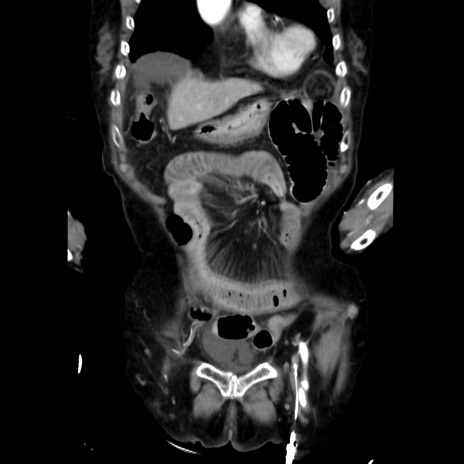

症例40(冠状断像)

【症例】90歳代女性

【主訴】腹痛・嘔吐

【現病歴】 食欲低下、嘔吐があり昨日他院受診。肺炎と診断され入院となる。入院後より腹部全体に圧痛あり。胃管留置され経過みていたが、症状持続するため、

当院転院となる。

【既往歴】胸椎圧迫骨折、胆石症

【身体所見】腹部:中央に激痛あり、圧痛あり、反跳痛不明

【データ】WBC 17100、CRP 18.82

冠状断像